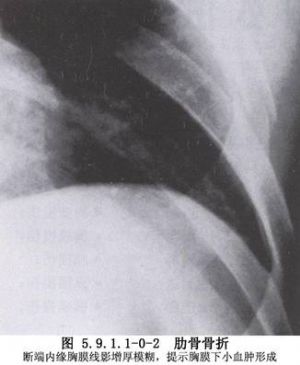

单纯肋骨骨折如未合并严重胸内脏器损伤,多不严重。疼痛是主要的临床表现,疼痛随呼吸、咳嗽及喷嚏而加重。常因疼痛不敢深呼吸及咳嗽,易使呼吸道分泌物潴留,引起肺部感染。骨折刺破胸膜和肺组织可发生气胸、血胸或皮下气肿及咯血。骨折处明显压痛,有时可触到骨折断端或可听到骨擦音。前后挤压胸廓,可引起胸壁疼痛,且与局部压痛点一致,为间接压痛阳性。X线检查不仅可以观察骨折情况,而且可以了解有无合并胸内脏器伤。如果肋骨骨折无明显移位,或肋骨骨折位于肋骨与肋软骨交界处,X线胸片上难以看出骨折线,可行超声检查或待3~6周后X线复查看见骨痂阴影。CT扫描对合并肺挫伤、肺内血肿及肺裂伤具有特殊的诊断价值。肋骨骨折的诊断并不困难,但应仔细全面检查,注意有无血胸、气胸及合并其他部位的损伤。X线检查应重复进行,以及时发现延迟性血胸、气胸、肺不张及肺部感染等(图5.9.1.1-0-1~5.9.1.1-0-3)。